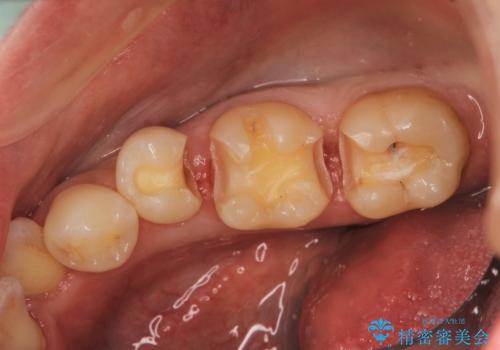

- 右下の奥の歯と歯の間に食べ物がつまること、つまったものがなかなか取れないことを主訴に来院されました。

右下6,7間に隙間があり、つめものの境目から虫歯になっていました。

セラミック希望とのことで、手前の歯も一緒に金属を外してセラミックにて修復することになりました。

セラミックでより自然な色合いに、かつ歯の形を修正することで物のつまりやすさを改善することもでき、大変満足していただけました。